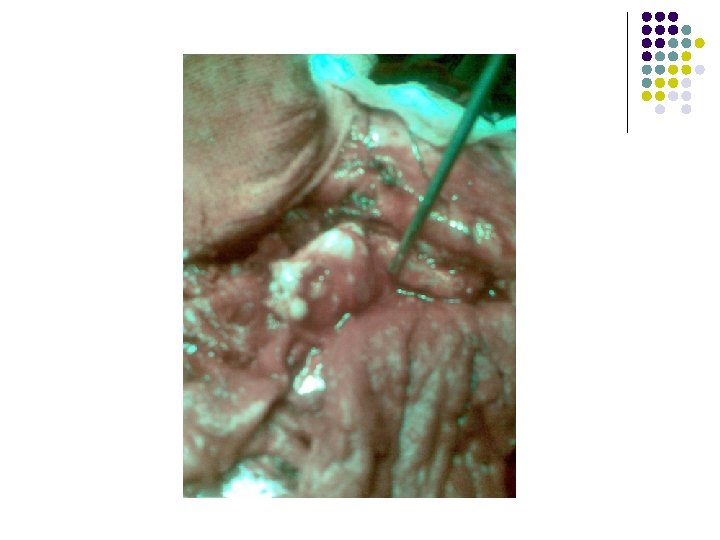

Treatment Transcranial Orbitotomy and Removal of the Tumour was done under G/A on 11 th December, 2011

Operative Procedure

Confirm Diagnosis by Histopathology Pleomorphic Adenoma